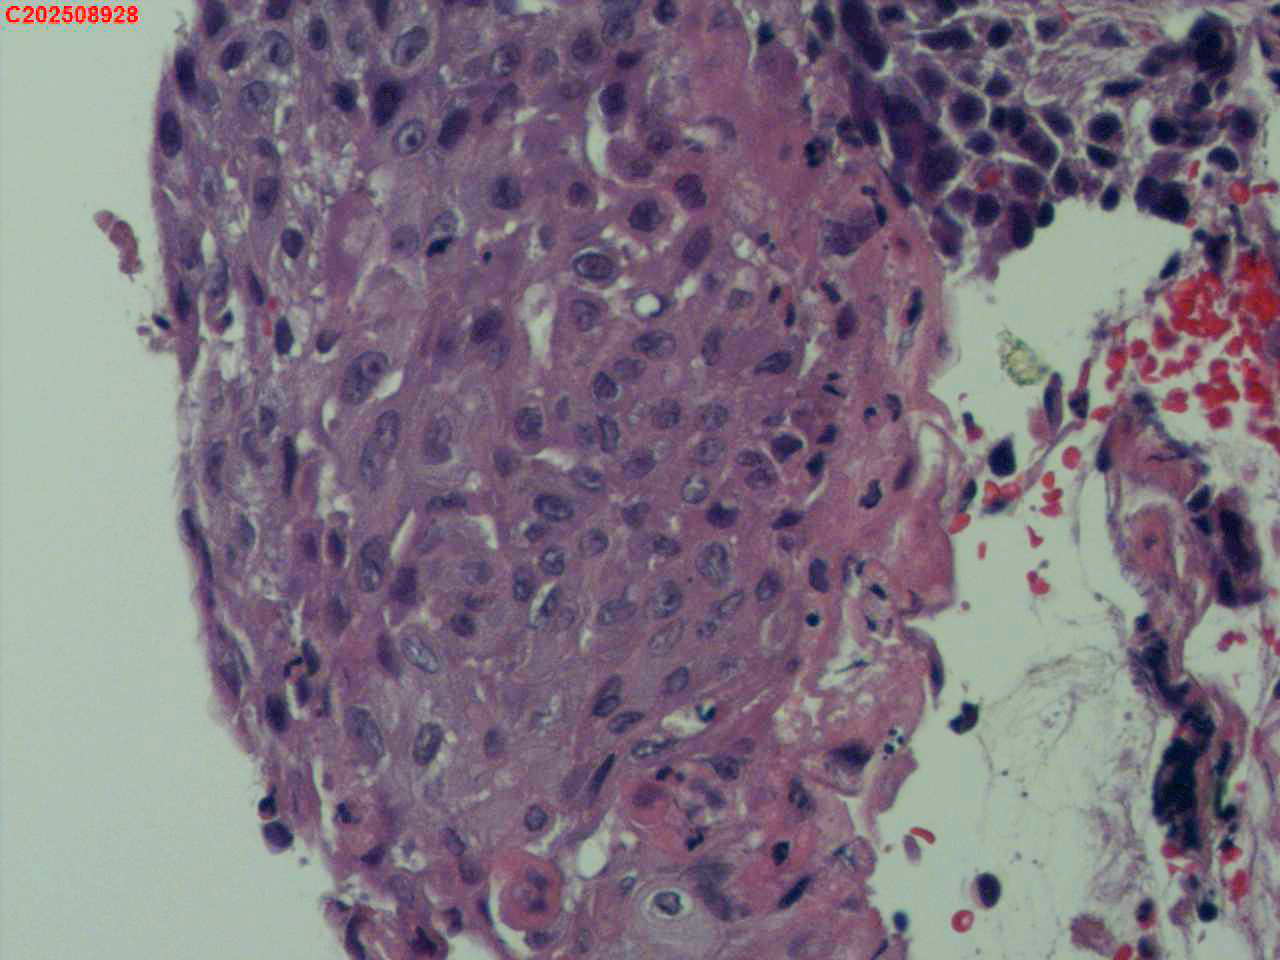

喉部右侧、声带下方咬检

男

56岁

喉Ca?

咳嗽

喉室内右侧声带下方新生物。

考虑鳞癌

鳞癌,有微浸润